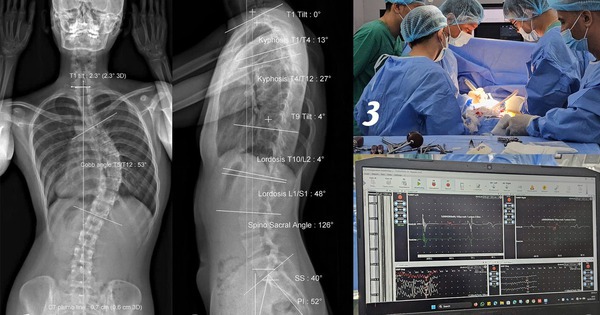

Trong 1 lần soi gương thấy dáng lưng có dấu hiệu bất thường, đến khi đi khám, cô gái 18 tuổi sốc khi biết bị vẹo cột sống ngực 53 độ.